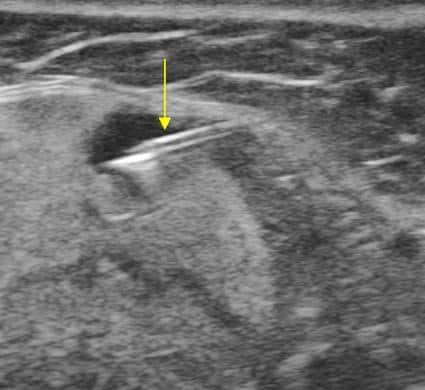

Hạch tuyến nước bọt

» Thông tin: Nữ giới – 66 tuổi.

» Lâm sàng: Sưng đau vùng góc hàm.

# Hạch lành tính ngoại vi tuyến nước bọt dưới hàm.